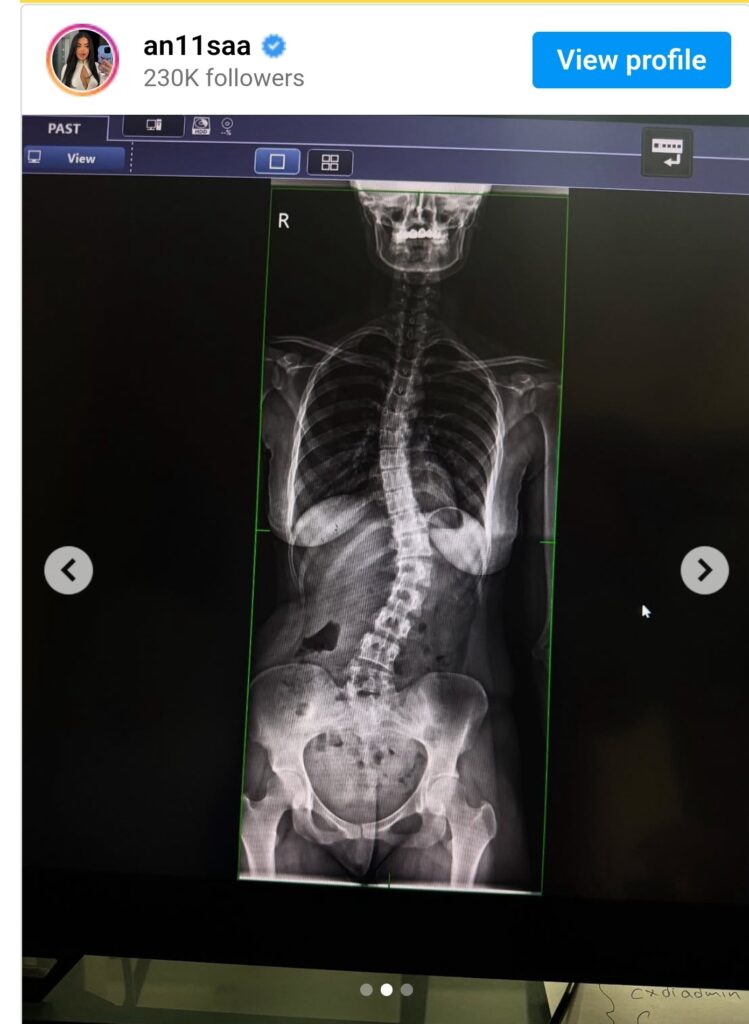

Ish banorja e BBVK i është nënshtruar operacionit për skoliozën.